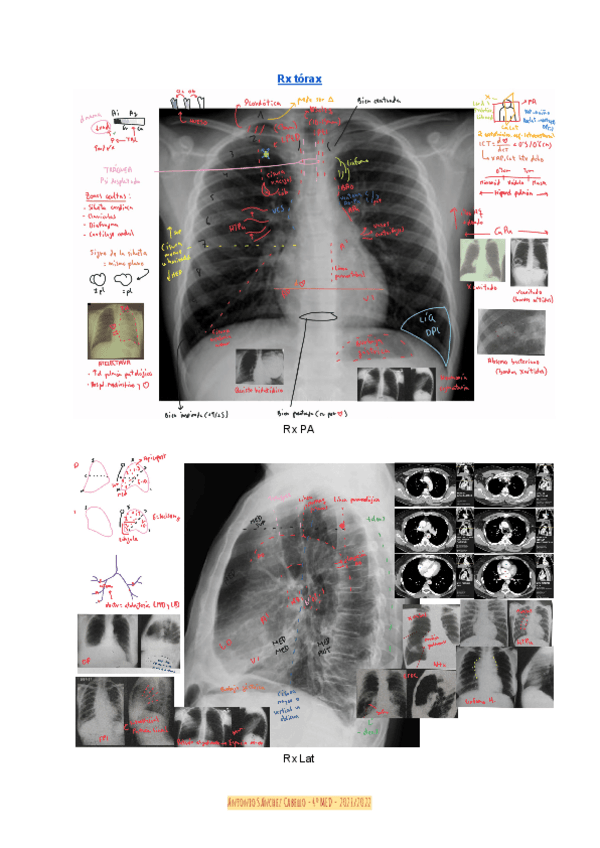

He publicado nuevos apuntes de 4º Radiología y Medicina Física: Temas-29-33-radiografia-del-torax.pdf

30 páginas

He publicado nuevos apuntes de 4º Radiología y Medicina Física: Resumen-Rx-torax.pdf

1 página